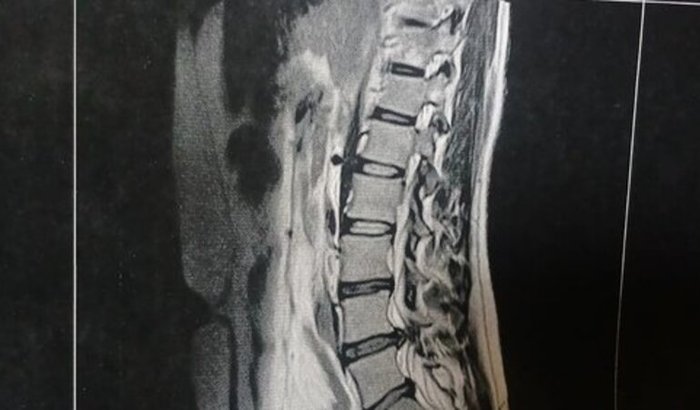

Olá, pessoal! Sou o Sebastião Fábio dos Santos, morador da comunidade rural Lagoa de Cima. Sempre trabalhei duro na roça, cortando madeira e realizando serviços que exigem muito da minha força física como a cavoeira que todos conhecem. Porém, nos últimos meses, venho enfrentando dores intensas na coluna. Fui internado várias vezes em busca de alívio, e após exames, descobri que preciso de uma cirurgia devido a lesões na coluna que não se resolveram com tratamento tradicional. Infelizmente, isso me deixou impossibilitado de trabalhar e de sustentar minha casa.